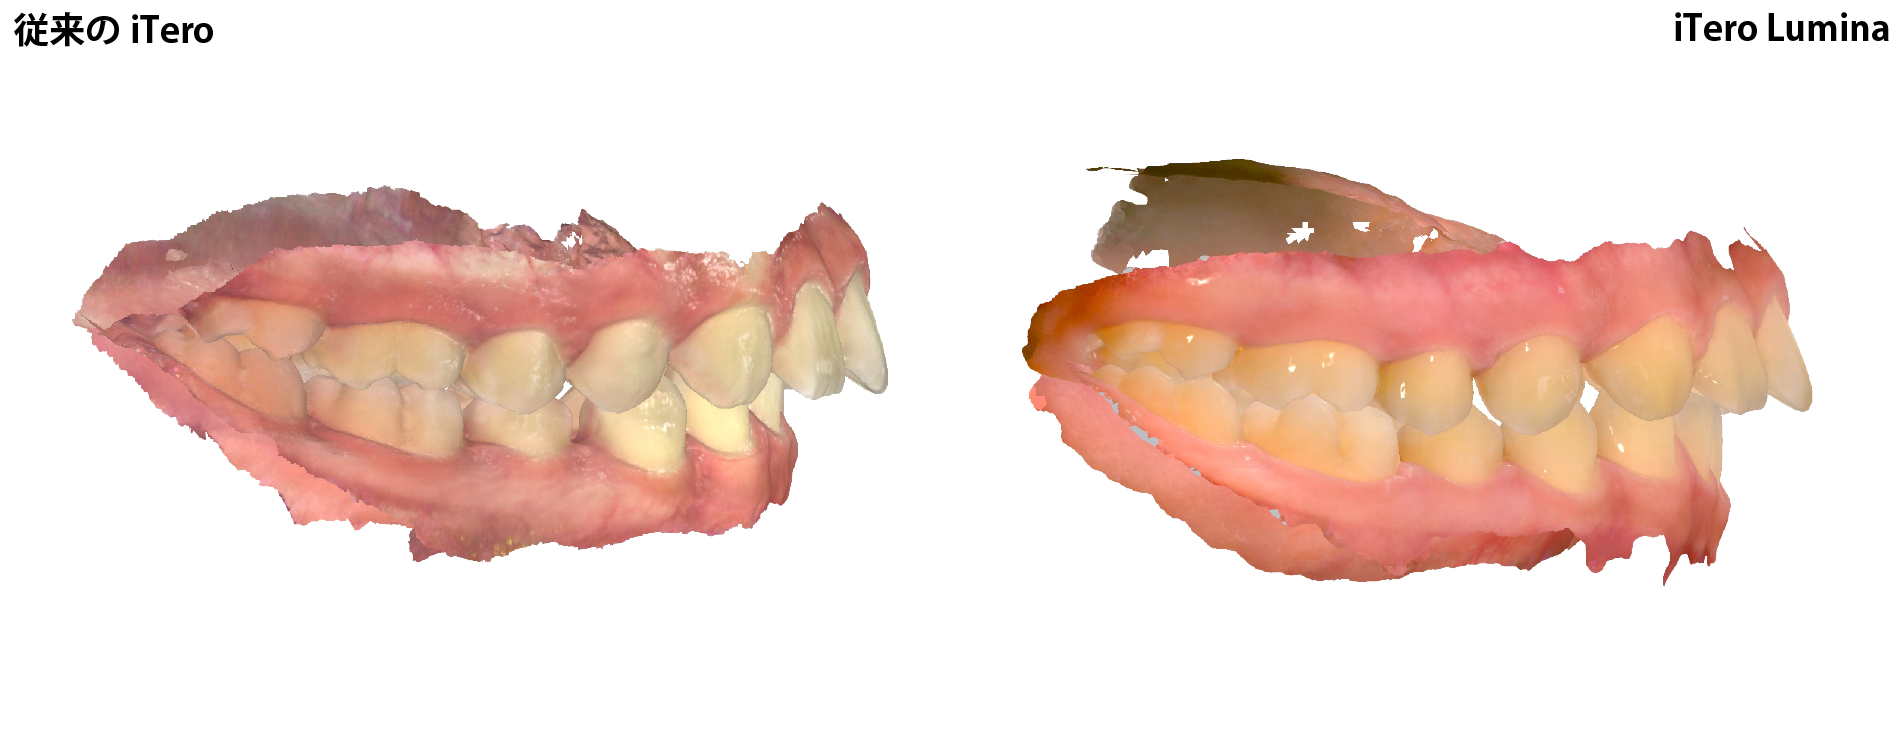

従来のiTero と iTero Lumina 比較画像

従来のiTero と iTero Lumina のスキャンデータ画像を比較すると明らかにその精細度に違いがあります。